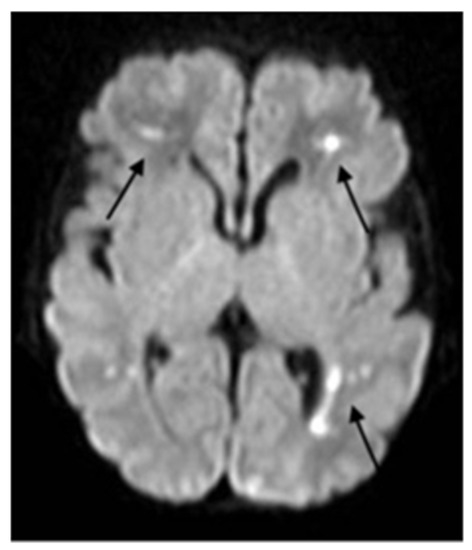

Severe COVID-19 Complicated by Cerebral Venous Thrombosis in a Newborn Successfully Treated with Remdesivir, Glucocorticoids, and Hyperimmune Plasma

2. Case Description